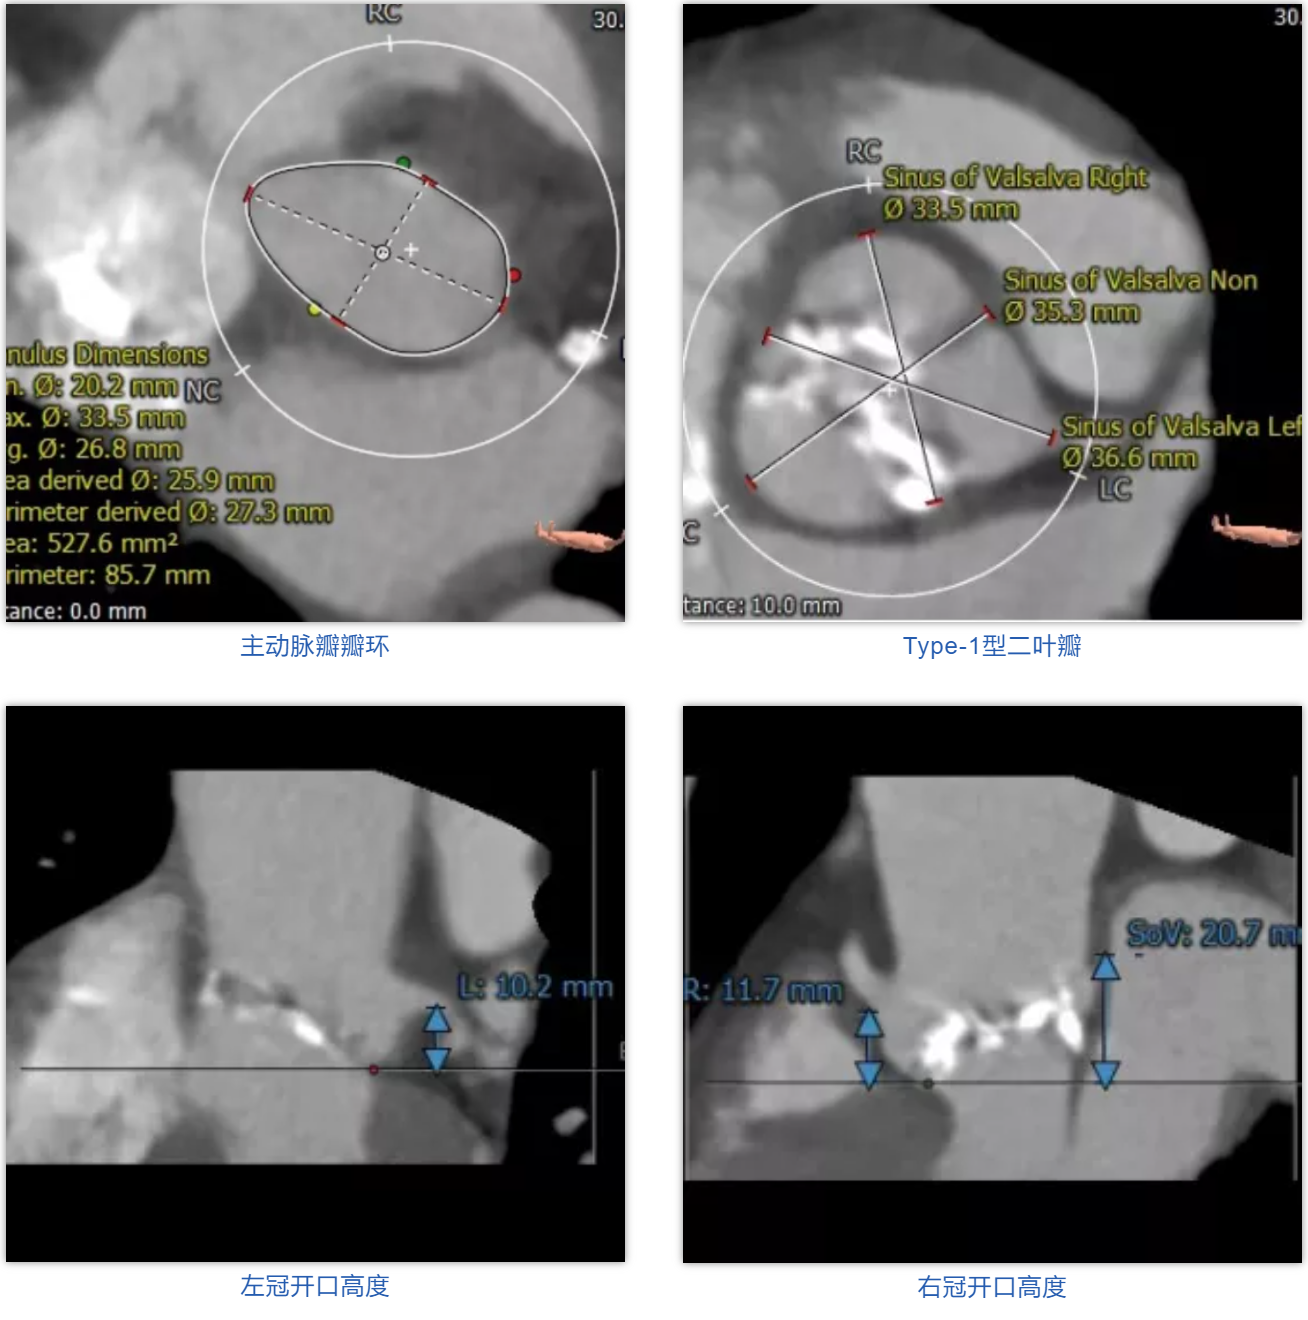

患者男性,67岁,因“劳累后胸闷4月余”入院,术前心脏超声提示主动脉瓣钙化,重度狭窄并轻-中度反流。患者STS评分11.0%,属于常规外科换瓣手术高风险。CT评估结果显示主动脉瓣为Type-1型二叶瓣,瓣叶增厚钙化,瓣环平均直径26.8mm,瓣环面积527.6mm²,面积径25.9mm。左冠脉开口高度10.2mm,右冠脉开口高度11.7mm。术前经详尽影像学重建、评估及病例讨论,测量瓣环直径、分析二叶瓣结构,评估冠脉梗阻风险后,计划植入25# Renatus介入主动脉瓣。